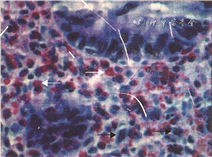

11例电子结肠镜检查均可见直肠结肠黏膜充血、水肿,肠黏膜糜烂8例,黏膜出血、溃疡灶各5例(图1)。组织病理学改变表现为肠黏膜炎性改变,结肠黏膜间质可见炎性细胞浸润,局灶区间质可见嗜酸性粒细胞浸润:5~30个/HPF不等(图2)。

AP主要病变在结肠,尤其是乙状结肠末段和直肠,呈灶性或弥漫性病变,内镜表现为肠黏膜充血、水肿、糜烂、灶性出血、溃疡等,组织学可见上皮层和固有层嗜酸性粒细胞浸润,部分患儿可有淋巴结增生病变,很少形成隐窝脓肿[1]。本组资料显示,11例AP患儿均可见直肠结肠黏膜不同程度的充血、水肿,8例伴黏膜糜烂,5例伴出血,5例伴溃疡。考虑到肠黏膜充血、肿胀,为防止检查造成进一步损伤,本组病例内镜检查范围只限于观察直肠和乙状结肠病变,病理显示肠黏膜间质可见炎性细胞浸润,以淋巴细胞或浆细胞为主,病灶区间质可见嗜酸性粒细胞浸润。需要注意的是,内镜检查和病理活检有助于AP的诊断与鉴别诊断,但不属于常规检查项目,当患儿通过回避可疑过敏原4周症状仍不能缓解,病情需要进一步诊断和鉴别诊断,需要明确嗜酸细胞性胃肠炎或食管炎、乳糜泻和食物蛋白诱导性小肠结肠炎等疾病时才有检查指征[1]。